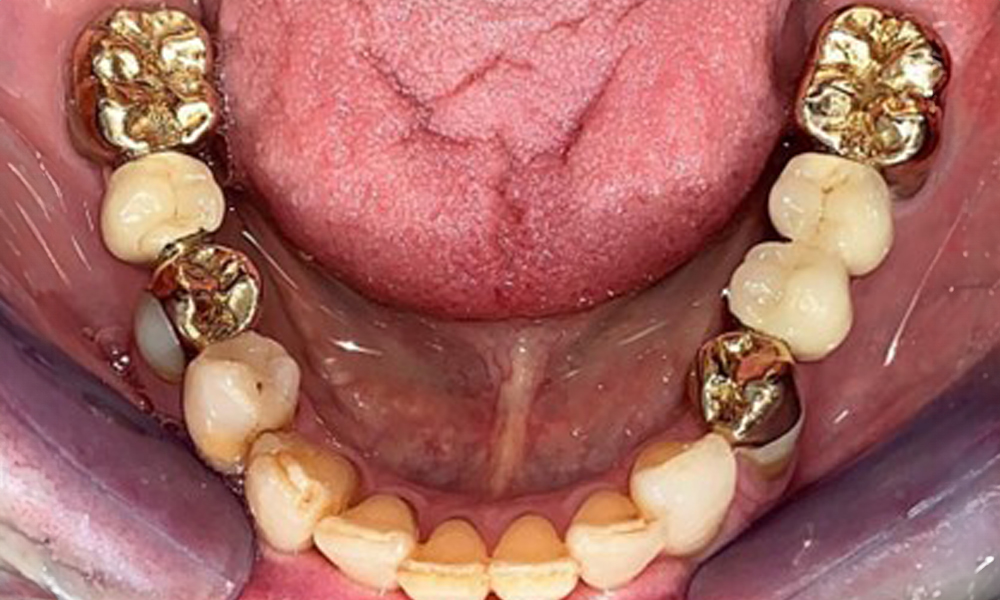

Occlusal view of the mandible.

Fig. 4: Occlusal view of the mandible.

The dental findings are as follows: Combined removable implant and tooth-supported telescopic prostheses on implants 15, 13, 21, 23, 24, 25 and tooth 11 (Fig. 1, Fig. 2, Fig. 3). The patient was fitted with a fixed mandibular denture. Adequate bridges were present over 37 to 34 and 45 to 47 (Fig. 4), the crown margins were intact and there were no active caries. A composite filling with a marginal gap was present on tooth 43. There was mandibular gingival recession, exposing 1 to 3 mm of root surface. This also applies to 11.